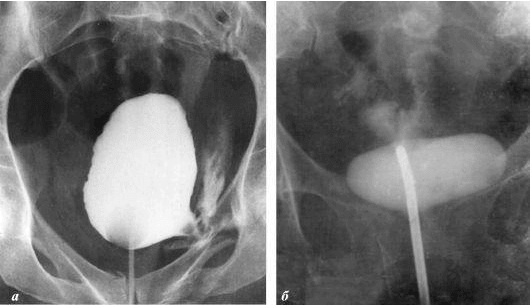

Dua t'ju tregoj disa foto per te demonstruar se cfare ndodh ne sistemin urogjenital dhe ne organet e tjera te nje burri qe nuk ben seks.

Ne foto shohim inflamacionin e prostates te shkaktuar nga stanjacioni i spermes (kur testikujt nuk zbrazen). Inflamacioni i vazhdueshem con fillimisht ne adenome te prostates dhe me pas ne kancer. Eshte pasoja e pashmangshme e prostatitit, dhe prandaj quhet "semundja e burrave te moshuar".

Kanceri i prostates te nje burre 58 vjec.